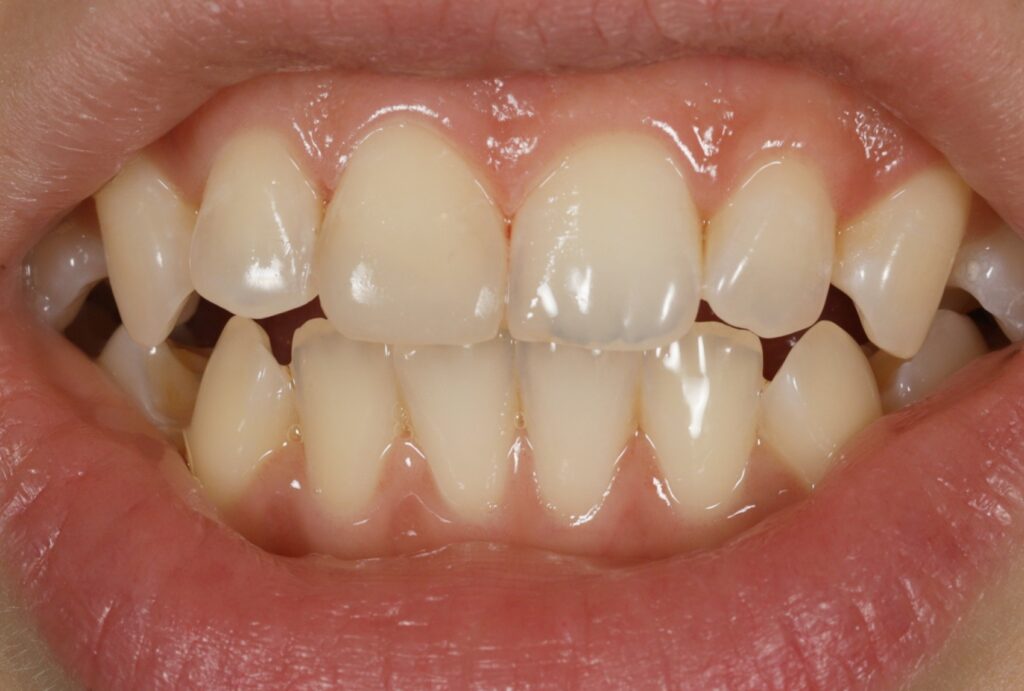

구강 내 모습을 확인해 보면

상악 중절치의 절단 부위가

약 1/3 정도 파절된 것을

관찰할 수 있는데요.

다행히 치수가 노출되지 않은

법랑질-상아질 파절로 확인됩니다.

대게 이러한 경우

초기에는 찬 음식이나

바람에 시린 증상이 나타났지만

심한 통증은 없을 수 있는데요.